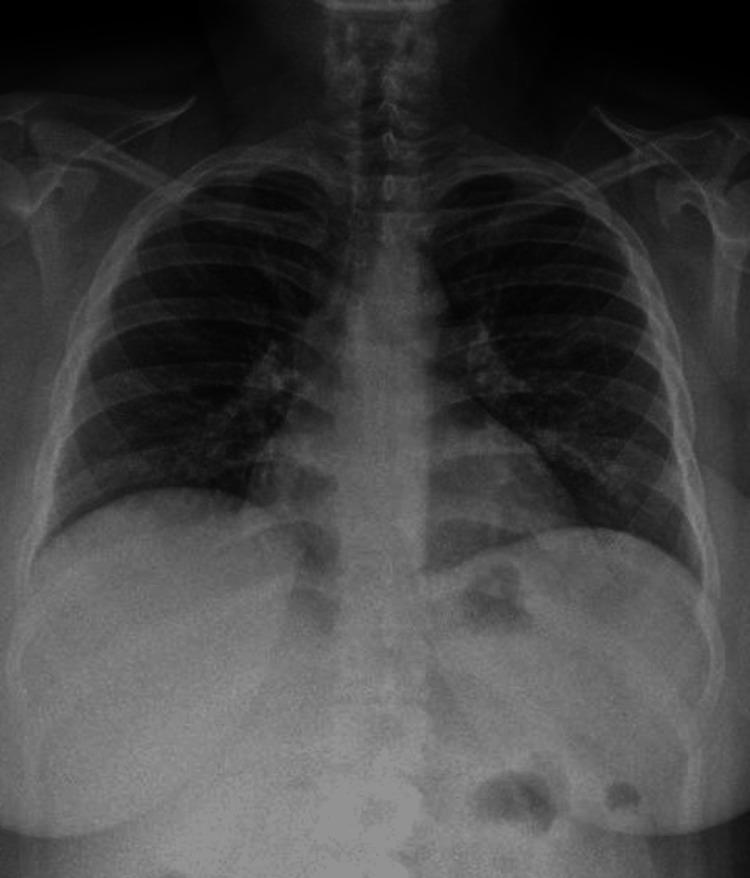

Cocaine, the second most used illicit drug, is associated with cardiovascular, pulmonary, and other complications. Lung involvement associated with cocaine use, also known as "crack lung syndrome" (CLS), can elicit new-onset and exacerbate chronic pulmonary conditions. A 28-year-old female with a history of chronic controlled asthma arrived at the Emergency Department (ED), referring to cocaine inhalation, followed by symptoms compatible with an asthmatic crisis, requiring immediate steroid and bronchodilator therapy. Radiological studies and bronchoscopy confirmed CLS diagnosis. Despite treatment with oxygen, bronchodilators, and steroids, the asthmatic crises persisted. However, after 48 hours, we observed a complete regression of the lung infiltrates. This case highlights the importance of clinical suspicion, bronchoscopy findings, and the potential co-occurrence of CLS with asthma exacerbations. While computed tomography (CT) scans can be helpful, they should not be the only tool to diagnose CLS. The successful management of CLS involves the use of bronchodilators, steroids, and oxygen therapy and abstaining from cocaine use. Researchers should conduct further studies to diagnose and treat CLS in conjunction with acute asthma symptoms to assist this patient population better.

可卡因是第二大常用非法药物,与心血管、肺部及其他并发症相关。与使用可卡因相关的肺部受累,也称为“快克肺综合征”(CLS),可引发新发疾病并加重慢性肺部疾病。一名有慢性可控性哮喘病史的28岁女性来到急诊科(ED),称吸入了可卡因,随后出现与哮喘发作相符的症状,需要立即进行类固醇和支气管扩张剂治疗。影像学检查和支气管镜检查确诊为CLS。尽管给予了吸氧、支气管扩张剂和类固醇治疗,但哮喘发作仍持续。然而,48小时后,我们观察到肺部浸润完全消退。该病例凸显了临床怀疑、支气管镜检查结果以及CLS与哮喘发作可能同时出现的重要性。虽然计算机断层扫描(CT)有助于诊断,但它不应是诊断CLS的唯一工具。CLS的成功治疗包括使用支气管扩张剂、类固醇和氧疗,并戒除可卡因使用。研究人员应开展进一步研究,以便结合急性哮喘症状诊断和治疗CLS,从而更好地帮助这一患者群体。